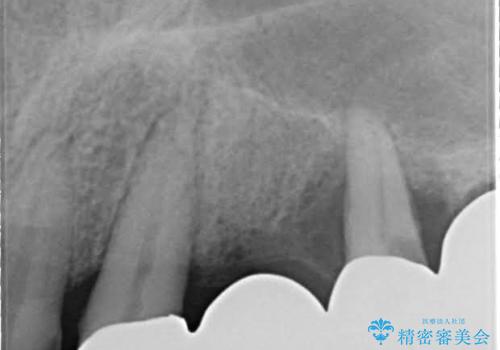

歯周病におかされた前歯の再建治療

- 歯周病により欠損が生じた歯槽骨、まずは再生治療をおこなう

→治癒後、確定外科を行い完全に歯周ポケットを除去し、最終的に歯周補綴をおこなう

歯周病が進行してしまうと、歯周外科による処置が不可欠になります。

様々なリスクがありますが、唯一歯周病を除去することが可能な手段です。